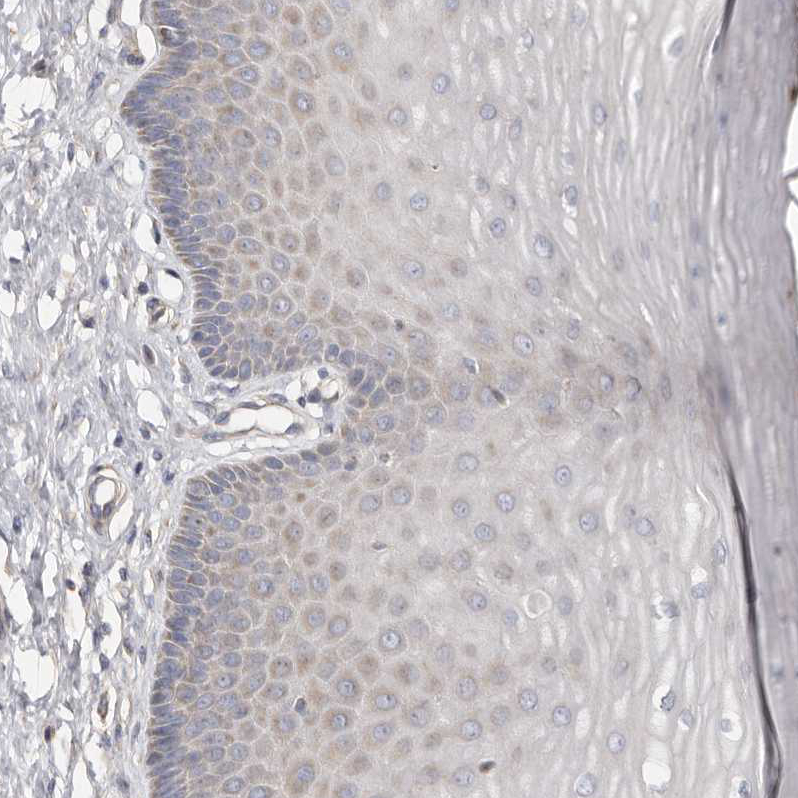

Immunohistochemical staining of human liver shows strong cytoplasmic positivity in hepatocytes.